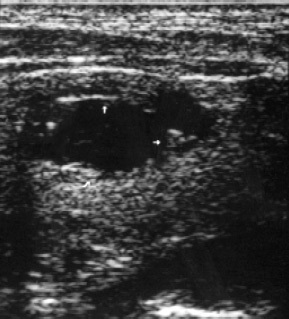

A vizsgálat a regionális nyirokmasszázs területeken a pajzsmirigy - okolotrahealnyh, mély nyaki (cervicalis), állkapocs alatti és kulcscsont feletti - kóros elváltozásokat csak a jobb kulcscsont feletti régióban. A jobb supraclavicularis zóna echografically különbséget három hypoechoic szilárd anyag képződésének 15,6x17,1, 21,7 mm-es és 29,4x24,1, amelyek közül az utolsó - tapintható (2. ábra).

Ábra. 2. Metastaticheskoie vereség szupraklavikuláris nyirokcsomók.